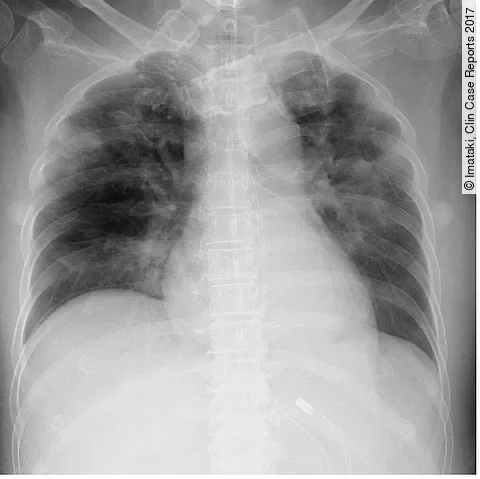

Ein 57-jähriger Mann stellt sich mit Müdigkeit, Gewichtsverlust und Nachtschweiß vor. In der Laboruntersuchung wurden eine normozytäre Anämie, Hypoalbuminämie, erhöhtes CRP und eine Leukozytose festgestellt.

Im MRT zeigt sich ein 7×5×4cm großer solider Tumor der linken Nebenniere mit inhomogenen Signalintensitäten in den nativen T1- und T2- gewichteten Sequenzen. Innerhalb des Tumors zeigten sich eine Diffusionsrestriktion sowie zentrale Hypointensitäten in der kontrastmittelangehobenen T1-Wichtung mit randständiger Anreicherung (Bildergalerie).